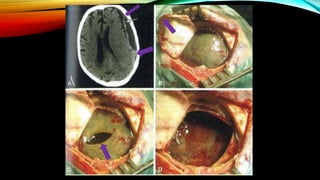

HEMATOMA SUBDURAL AGUDO

• Incidencia: 30%

• Mortalidad: 40-60%

• Clinica: deterioro de conciencia

(EG: < 8, 30-80%)

• Lesiones asociadas: muy frecuente

(solo 30 -40 % aislada); contusion

hemorrágica (+%), HSA, EDH, lesiones

extracraneales

Indicaciones de cirugía precoz: deterioro

clínico en 2 – 4 horas

Tratamiento Qx: grosor de hematoma > 10 mm o DLM > 5 mm se debe evacuar

independientemente EG.

Grosor <10 mm y DLM <5 mm: EG ↓ 2, y / o las pupilas son asimétricas o fijas y dilatadas, y / o

PIC es> 20 mm Hg.

Avascular rica en colágeno (cortical), en contacto con

la aracnoides, que es fina

Con frágiles vasos sinusoidales, pericitos y músculo liso distribuido

irregularmente y células inflamatorias, todo producto de una

estrecha correlación(dural), más gruesa

HEMATOMA SUBDURAL CRÓNICO

Con frecuencia encontrado en Neurocirugía,

especialmente en los ancianos, con una incidencia de

58 / 100.000 personas al año en personas de 70 años

de edad

Aunque CDSS es comúnmente encontrado en

Neurocirugía, todavía no existe un consenso en cuanto

a la técnica quirúrgica óptima para el tratamiento

Las tasas de recurrencia, sin embargo, puede ser alta,

con tasas reportadas hasta el 33%